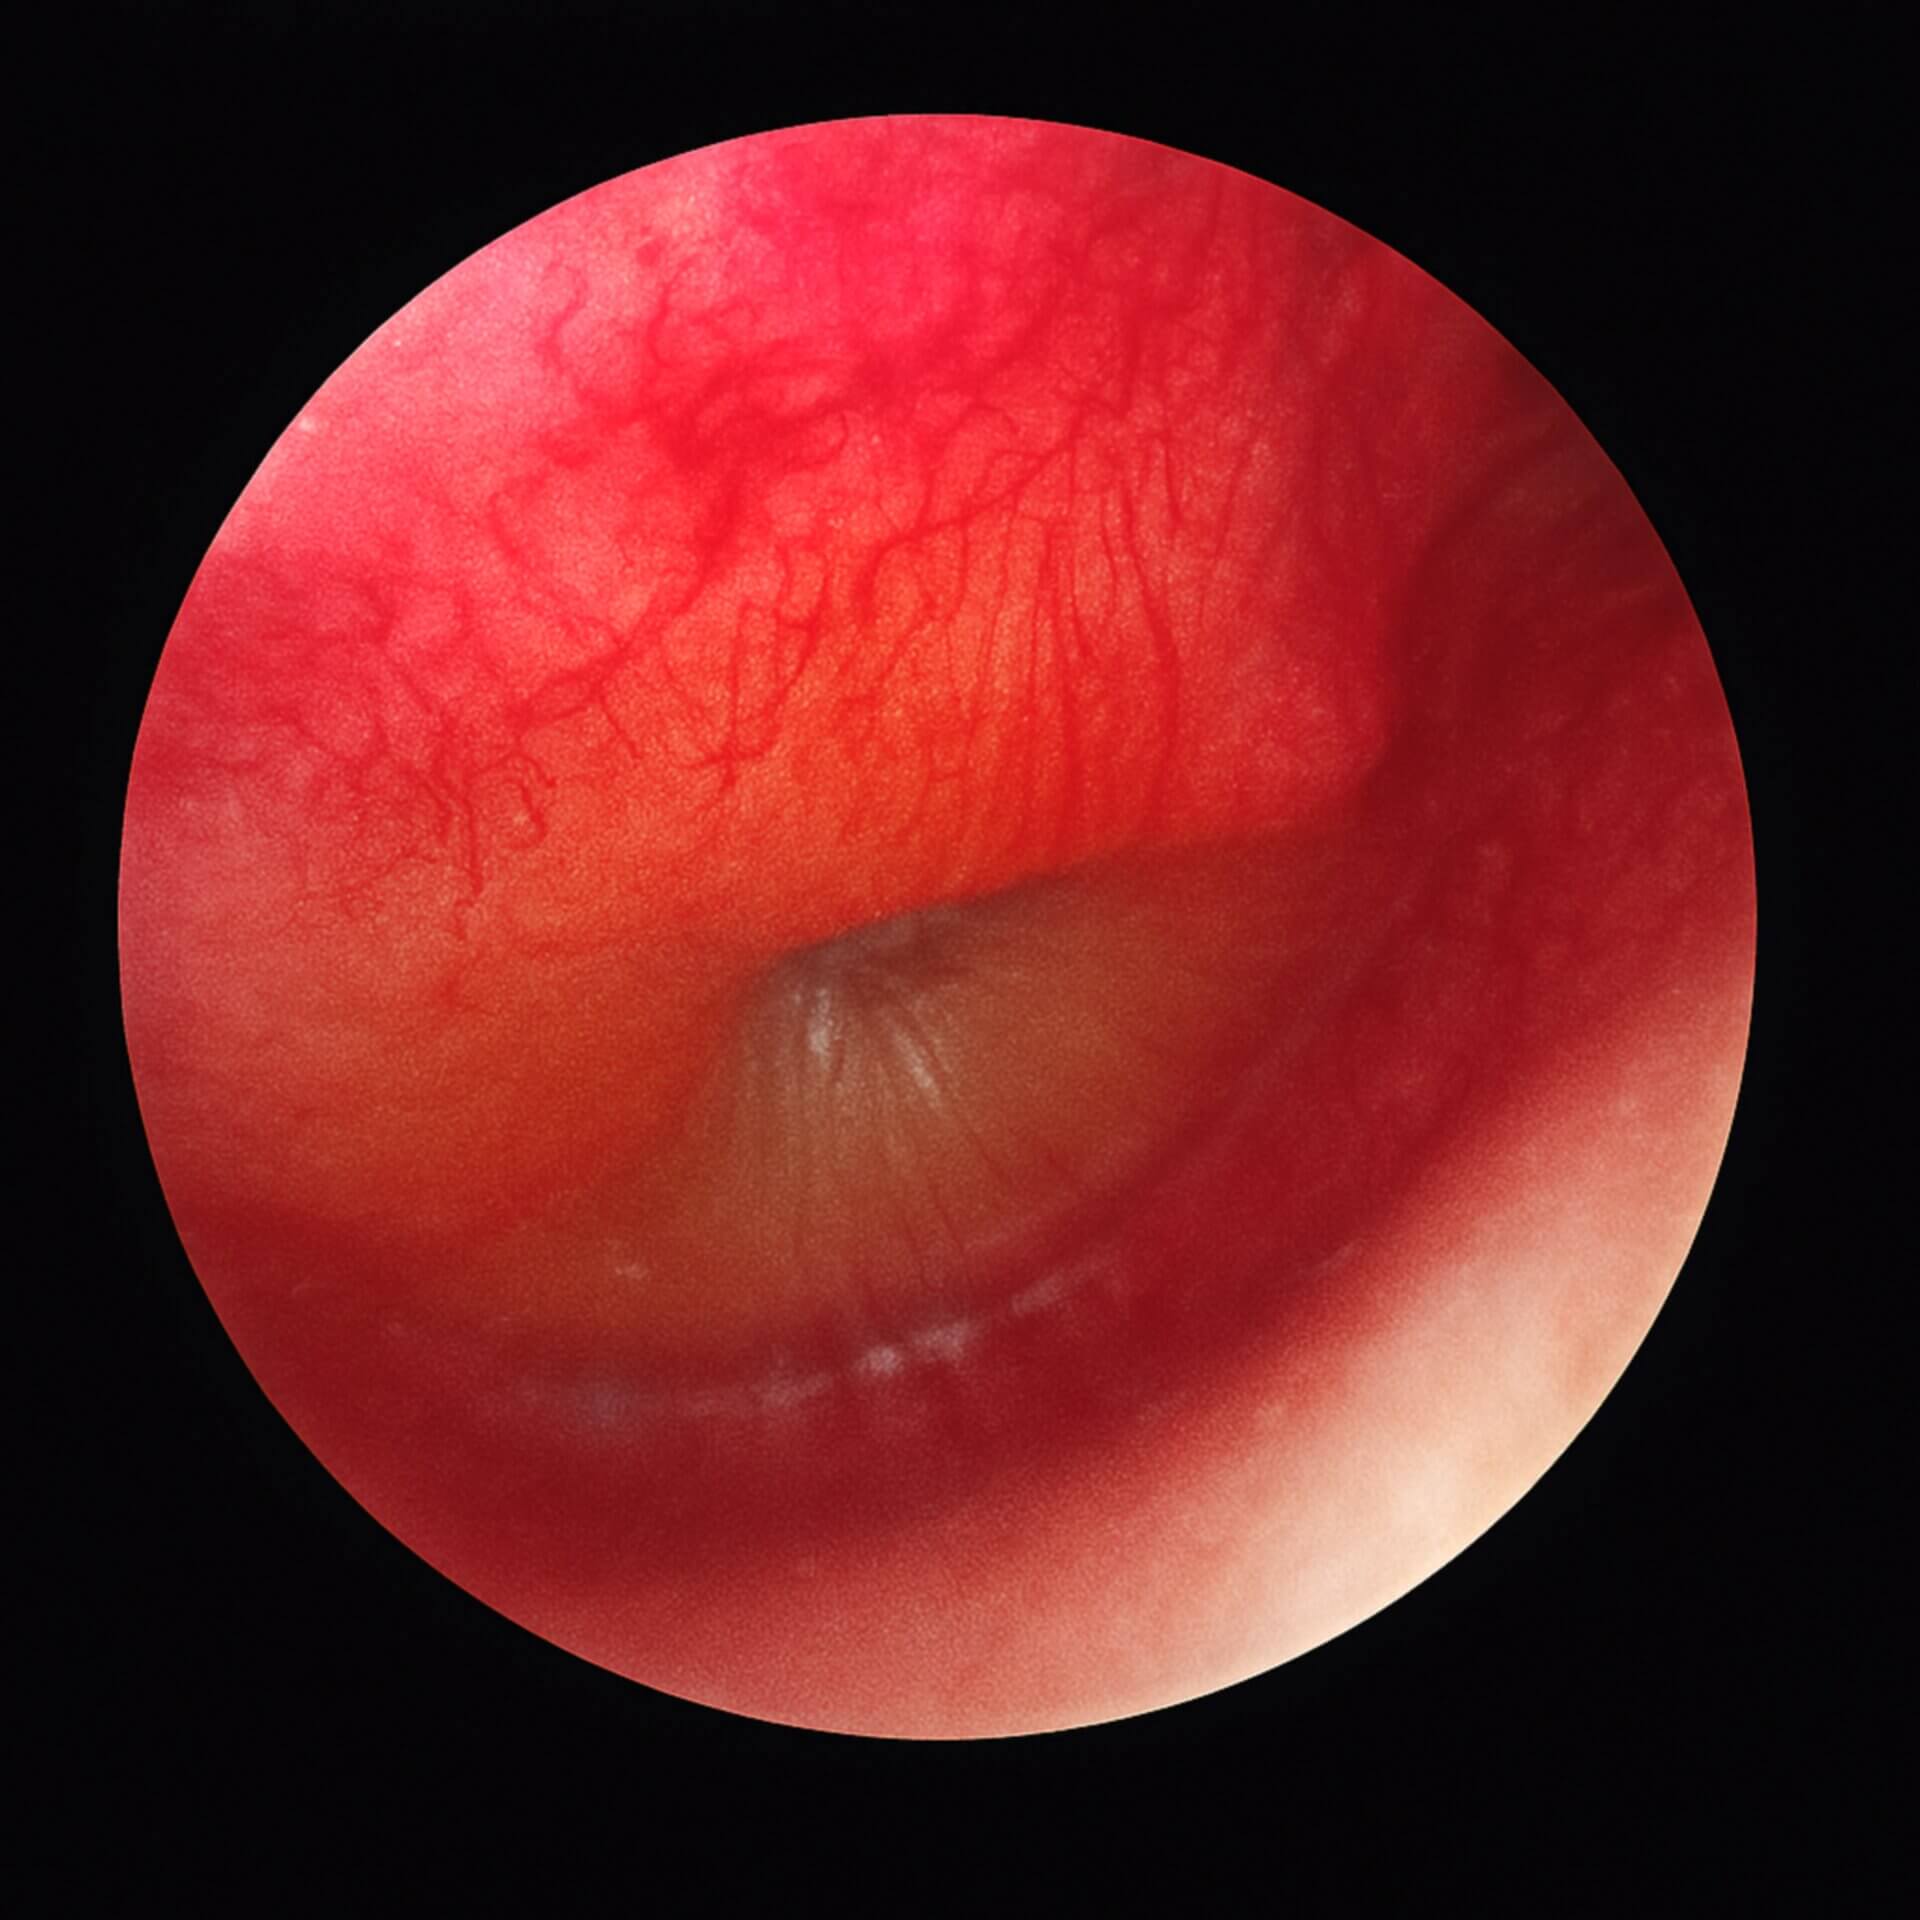

Im Otoskopiebefund zeigen sich:

Vermehrte Gefäßzeichnung, zunächst zentral am Hammergriff, später radiär ausstrahlend auch in der Peripherie des Trommelfells.